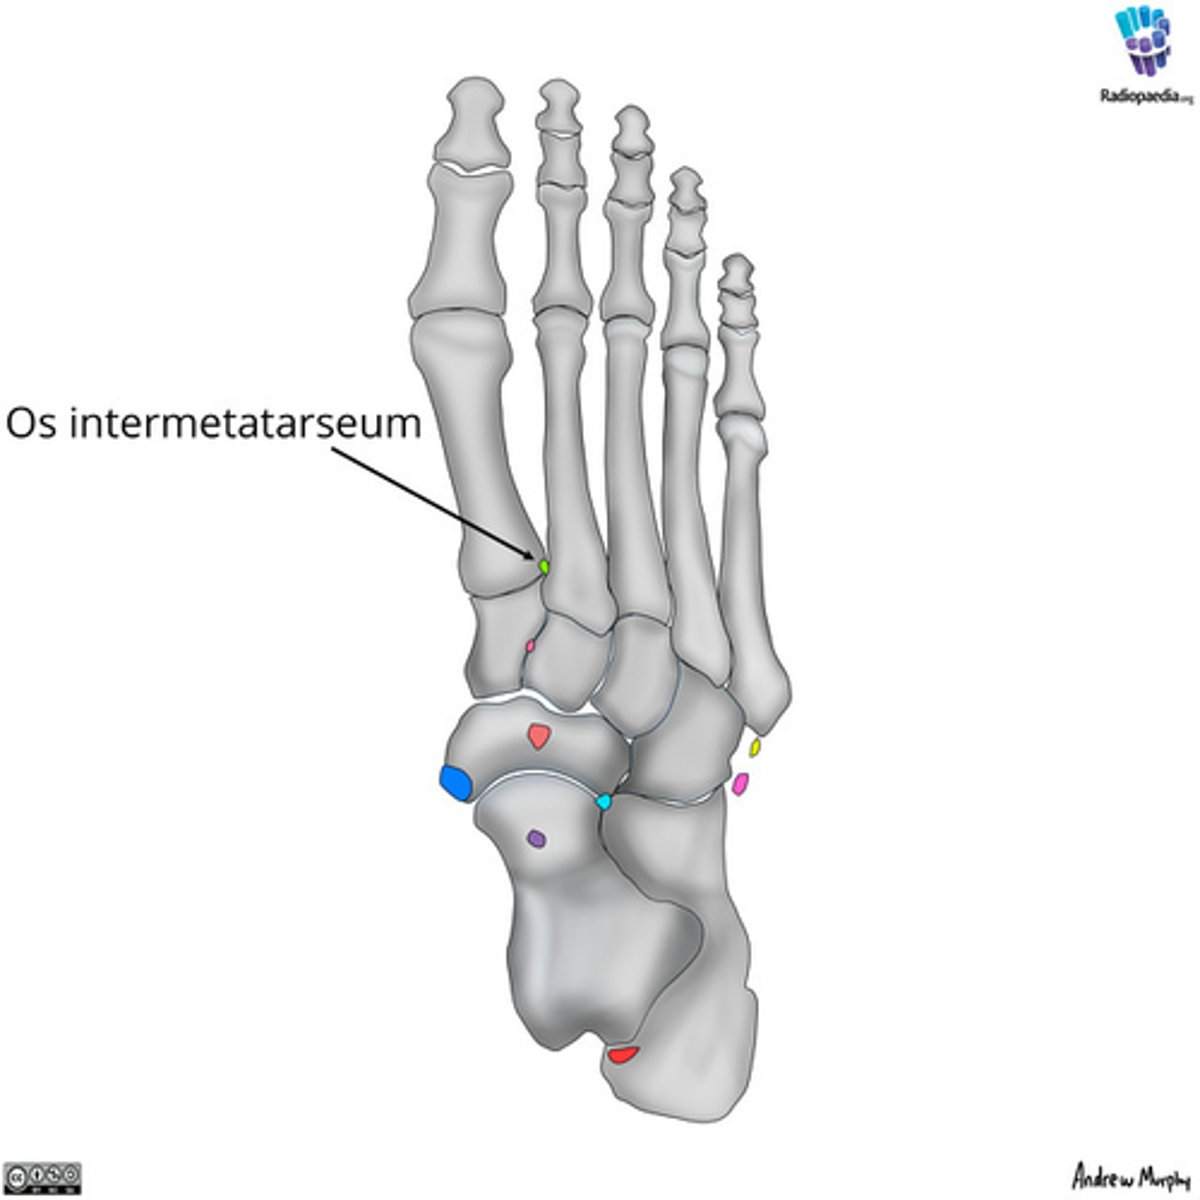

Artt. tarsometatarseae

Art. Plana

Artt. intermetatarseae